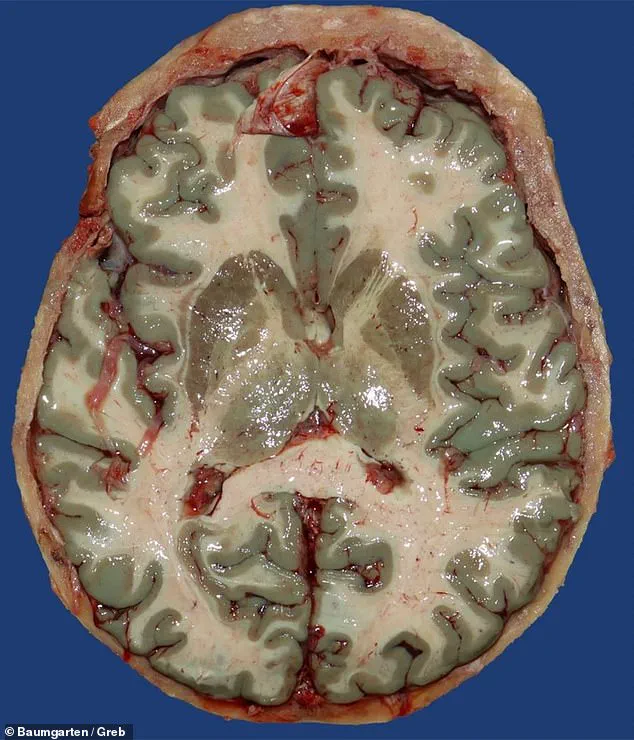

The findings, which emerged during an autopsy on a 72-year-old man whose brain was discovered to be an unusual shade of blue, have prompted a broader investigation into the dye’s effects on human tissue.

The team scoured their database of 15,820 autopsy records spanning two decades and identified 11 cases where organs such as the brain, heart, lungs, and pancreas exhibited a ‘blue-green,’ ‘greenish,’ or ‘turquoise’ hue.

The researchers emphasized that the blue hue darkened further during autopsies when exposed to air, but this effect was unrelated to the causes of death.